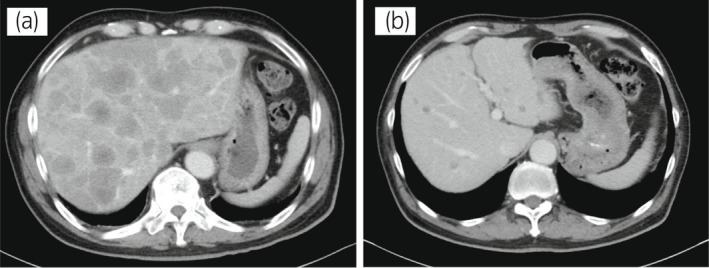

70 歲男性被診斷為轉(zhuǎn)移性 PC,cT3bN1M1b,Gleason 評(píng)分(GS)為 4 + 5 = 9,前列腺特異性抗原(PSA)水平為 40.8ng/ml,3 年前伴有胸椎轉(zhuǎn)移。 對(duì)前列腺進(jìn)行聯(lián)合雄激素阻斷 (CAB) 治療和質(zhì)子放射治療 (78.0Gy/39fr)。 PSA 水平降至 <0.01ng/ml,CAB 在 2.5 年后停止。 停止 CAB 五個(gè)月后,他出現(xiàn)背痛,PSA <0.01 ng/ml。 計(jì)算機(jī)斷層掃描 (CT) 掃描檢測(cè)到多處肝、骨和淋巴結(jié)轉(zhuǎn)移,神經(jīng)元特異性烯醇化酶 (NSE) 水平高達(dá) 171ng/ml(圖 1a)。 骨轉(zhuǎn)移活檢顯示神經(jīng)內(nèi)分泌前列腺癌 (NEPC) 的診斷(圖 2),患者被轉(zhuǎn)診至佳學(xué)基因合作醫(yī)院。 內(nèi)分泌腫瘤正確治療醫(yī)生用順鉑、依托泊苷和亮丙瑞林治療。 第三個(gè)療程后,轉(zhuǎn)移部位明顯縮?。▓D 1b)。 順鉑和依托泊苷治療 1 年,但患者因神經(jīng)病變要求停藥。 他開(kāi)始服用恩雜魯胺。 治療 3 個(gè)月后,患者出現(xiàn)背痛和左鎖骨下淋巴結(jié)腫大(圖 3a)。 肝轉(zhuǎn)移保持不變,順鉑治療后縮小。 通過(guò)腫瘤正確用藥850基因檢測(cè)證實(shí)了 BRCA2 突變。根據(jù)基因檢測(cè)結(jié)果,主治腫瘤科醫(yī)生給予了奧拉帕尼。 三個(gè)月后,背痛好轉(zhuǎn),淋巴結(jié)轉(zhuǎn)移縮小,確定為部分緩解(PR)(圖3b)。 肝轉(zhuǎn)移灶保持不變。

圖1:病例1.順鉑和依托泊苷三個(gè)療程前后的腹部CT圖像。 (a) 治療前和 (b) 治療后。